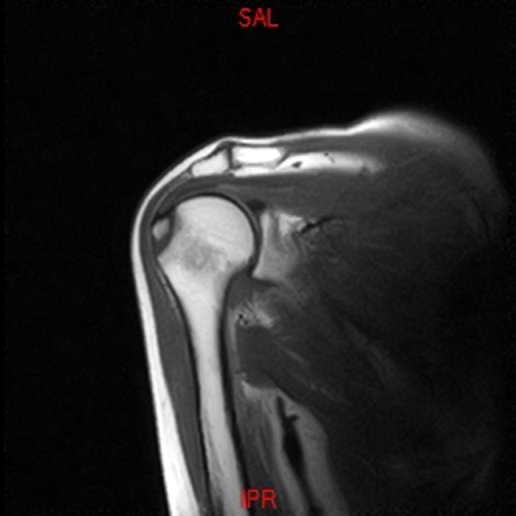

• Resonancia PATOLÓGICA DE HOMBRO - FRACTURA TROQUITER -  COR T1

• Resonancia PATOLÓGICA DE HOMBRO - FRACTURA TROQUITER Y EDEMA OSEO -  COR T2 WF